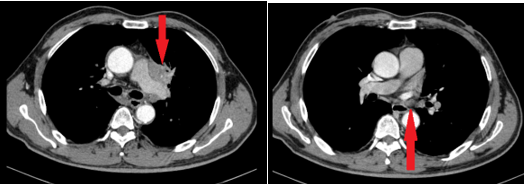

- Chụp cắt lớp vi tính lồng ngực: Hình ảnh khối nhu mô thùy trên phổi trái kích thước 38x38x59 mm, bờ tua gai co kéo gây giãn các nhánh phế quản lân cân, ngấm thuốc mạnh không đều sau tiêm, xâm lấn trung thất. Hạch trung thất dưới carina, dọc quai động mạch chủ và rốn phổi trái, hạch lớn nhất kích thước 14x11 mm.

Hình 2: Hình ảnh cắt lớp vi tính lồng ngực lúc mới: khối thùy trên phổi trái xâm lấn trung thất (mũi tên đỏ).

Hình 3: Hình ảnh cắt lớp vi tính lồng ngực lúc mới chẩn đoán: hình ảnh hạch trung thất cạnh quai động mạch chủ (hình bên trái), hạch rốn phổi trái (hình bên phải).